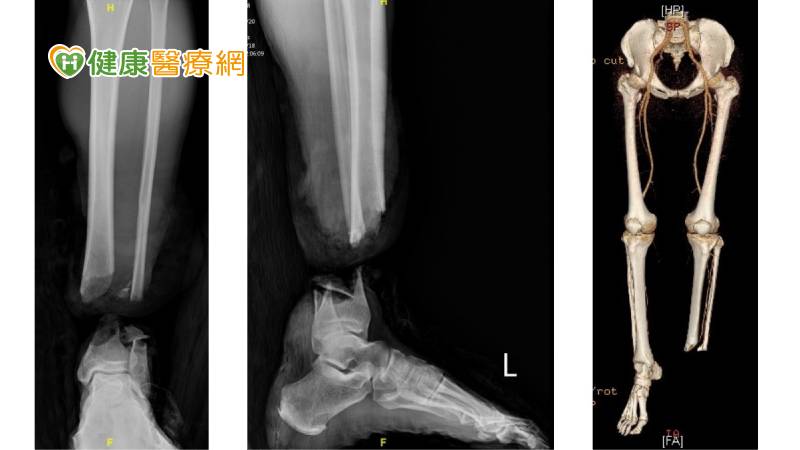

▲▼緊急手術先由骨科醫師將骨頭復位採取外固定,再由整形外科醫師接手迅速進行顯微重建手術。(基隆長庚醫院提供)

回顧意外當下,吳先生第一時間利用潛水裝備,用力拉緊斷口止血,記下斷肢沉沒地點,並迅速返回岸上急救,「事發當下,只想著奮力游回岸上,保全性命。回到岸上,也氣力放盡了,之後就被送至基隆長庚醫院。」被截斷的左小腿距離岸邊約50米遠、位於水下5米深,由另一位教練潛下水中,順利找到斷肢送到醫院。基隆長庚醫院整形外科藍靖宇醫師指出,斷肢有潛水裝備包覆,因此沒有感染。船艇螺旋槳完全截斷左小腿,斷口完整,但有粉碎性骨折與血管創傷。當天的緊急手術先由骨科醫師陳建豪將骨頭復位採取外固定,再由整形外科醫師接手迅速進行顯微重建手術,需要高度的技術和精準性,因為不僅要將患者的小腿成功植回,還要確保成功植回後能恢復日常生活,甚至繼續從事潛水活動的功能性。

顯微重建手術耗時4到6個小時,先從患者正常的右小腿取下25至30公分的靜脈血管做移植,再重建斷肢左小腿的前及後側的2套血液循環系統,同時也重新吻合主要的運動及感覺神經,並修復了小腿包含前側、後側、外側幾乎所有的肌肉與肌腱。術後,醫療團隊除了傷口照護,也替患者制定了個人化的康復計畫,結合物理治療和康復護理,以確保患者能夠在康復過程中達到最佳效果。基隆長庚外科部副部主任陳志豪表示,這種綜合治療的方法,不僅促進患者的身體康復,還同時關注患者心理健康。他強調,手術成功除了治療技術,也歸功於患者積極配合治療,是康復的關鍵所在。